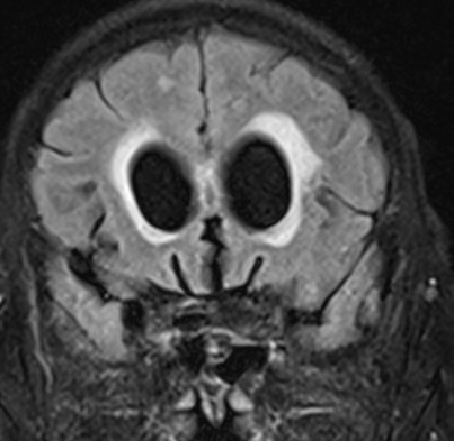

2015-4-1 MRI

2015-4-1